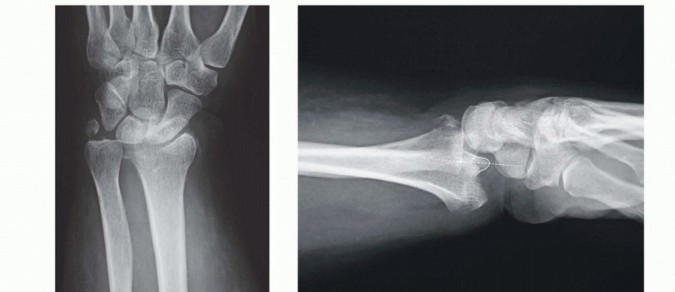

### FIG 5 • A. Carpal facet horizon (arrows). Used to differentiate between the volar and dorsal rim on the PA projection. B. Origin of carpal facet horizon. The carpal facet horizon is formed by that part of the articular surface that is parallel to the x-ray beam and depends on whether the articular surface is in volar or dorsal tilt. C. Normal teardrop angle. D. Depressed teardrop angle in this case is caused by axial instability of the volar rim. E. Normal articular congruency. F. Abnormal articular congruency, indicating disruption across the volar and dorsal surfaces of the lunate facet. G. AP interval is the point-to-point distance between the corners of the dorsal and volar rim. H. DRUJ interval. I. Normal lateral carpal alignment. J. Dorsal subluxation of the carpus. Congruency of the articular surface ( FIG 5E,F). The subchondral outline of the articular surface of the distal radius is normally both congruent and concentric with the subchondral outline of the base of the lunate; a uniform joint interval should be present between the radius and lunate along the entire articular surface. When the joint interval between these articular surfaces is not uniform, discontinuity and disruption of the lunate facet has occurred. Anteroposterior (AP) distance (normal: females 18 ± 1 mm, males 20 ± 1 mm; FIG 5G). The AP distance is the point-to-point distance from the dorsal to palmar rim of the lunate facet. It is best evaluated on the 10- degree lateral view. Widening of the AP distance implies discontinuity of the volar and dorsal portion of the lunate facet. 80 DRUJ interval ( FIG 5H). The DRUJ interval measures the degree of apposition between the head of the ulna and the sigmoid notch (normal: 2 mm or less). This parameter is best measured with the forearm in neutral rotation. Significant widening of the DRUJ interval implies disruption of the DRUJ capsule and TFCC. Coronal malalignment of the distal radial fragment is often suggested by widening of the DRUJ interval. Lateral carpal alignment ( FIG 5I,J). On the 10-degree lateral view and with the wrist in neutral position, the rotational center of the capitate normally aligns with a line extended from the volar surface of the radial shaft. Dorsal rotation of the volar rim results in a dorsal shift of lateral carpal alignment as the carpus subluxes dorsally. This may place the flexor tendons at a mechanical disadvantage, affecting grip strength. In addition to injury films, reassessing radiographs after reduction can be very helpful in determining the personality and specific components of a particular fracture. Computed tomography (CT) scans allow higher resolution and definition of fracture characteristics, particularly for highly comminuted fractures. Preferably, an attempt at closed reduction before obtaining a CT scan will help limit distortion of the image. CT scans are particularly helpful for visualizing intra-articular fragments as well as DRUJ disruption and incongruity of the sigmoid notch. Clinical evaluation of the carpus, interosseous membrane, and elbow, combined with radiographic studies when needed, should be included to identify the presence of other injuries that may affect the decision for a particular treatment. ## SURGICAL MANAGEMENT